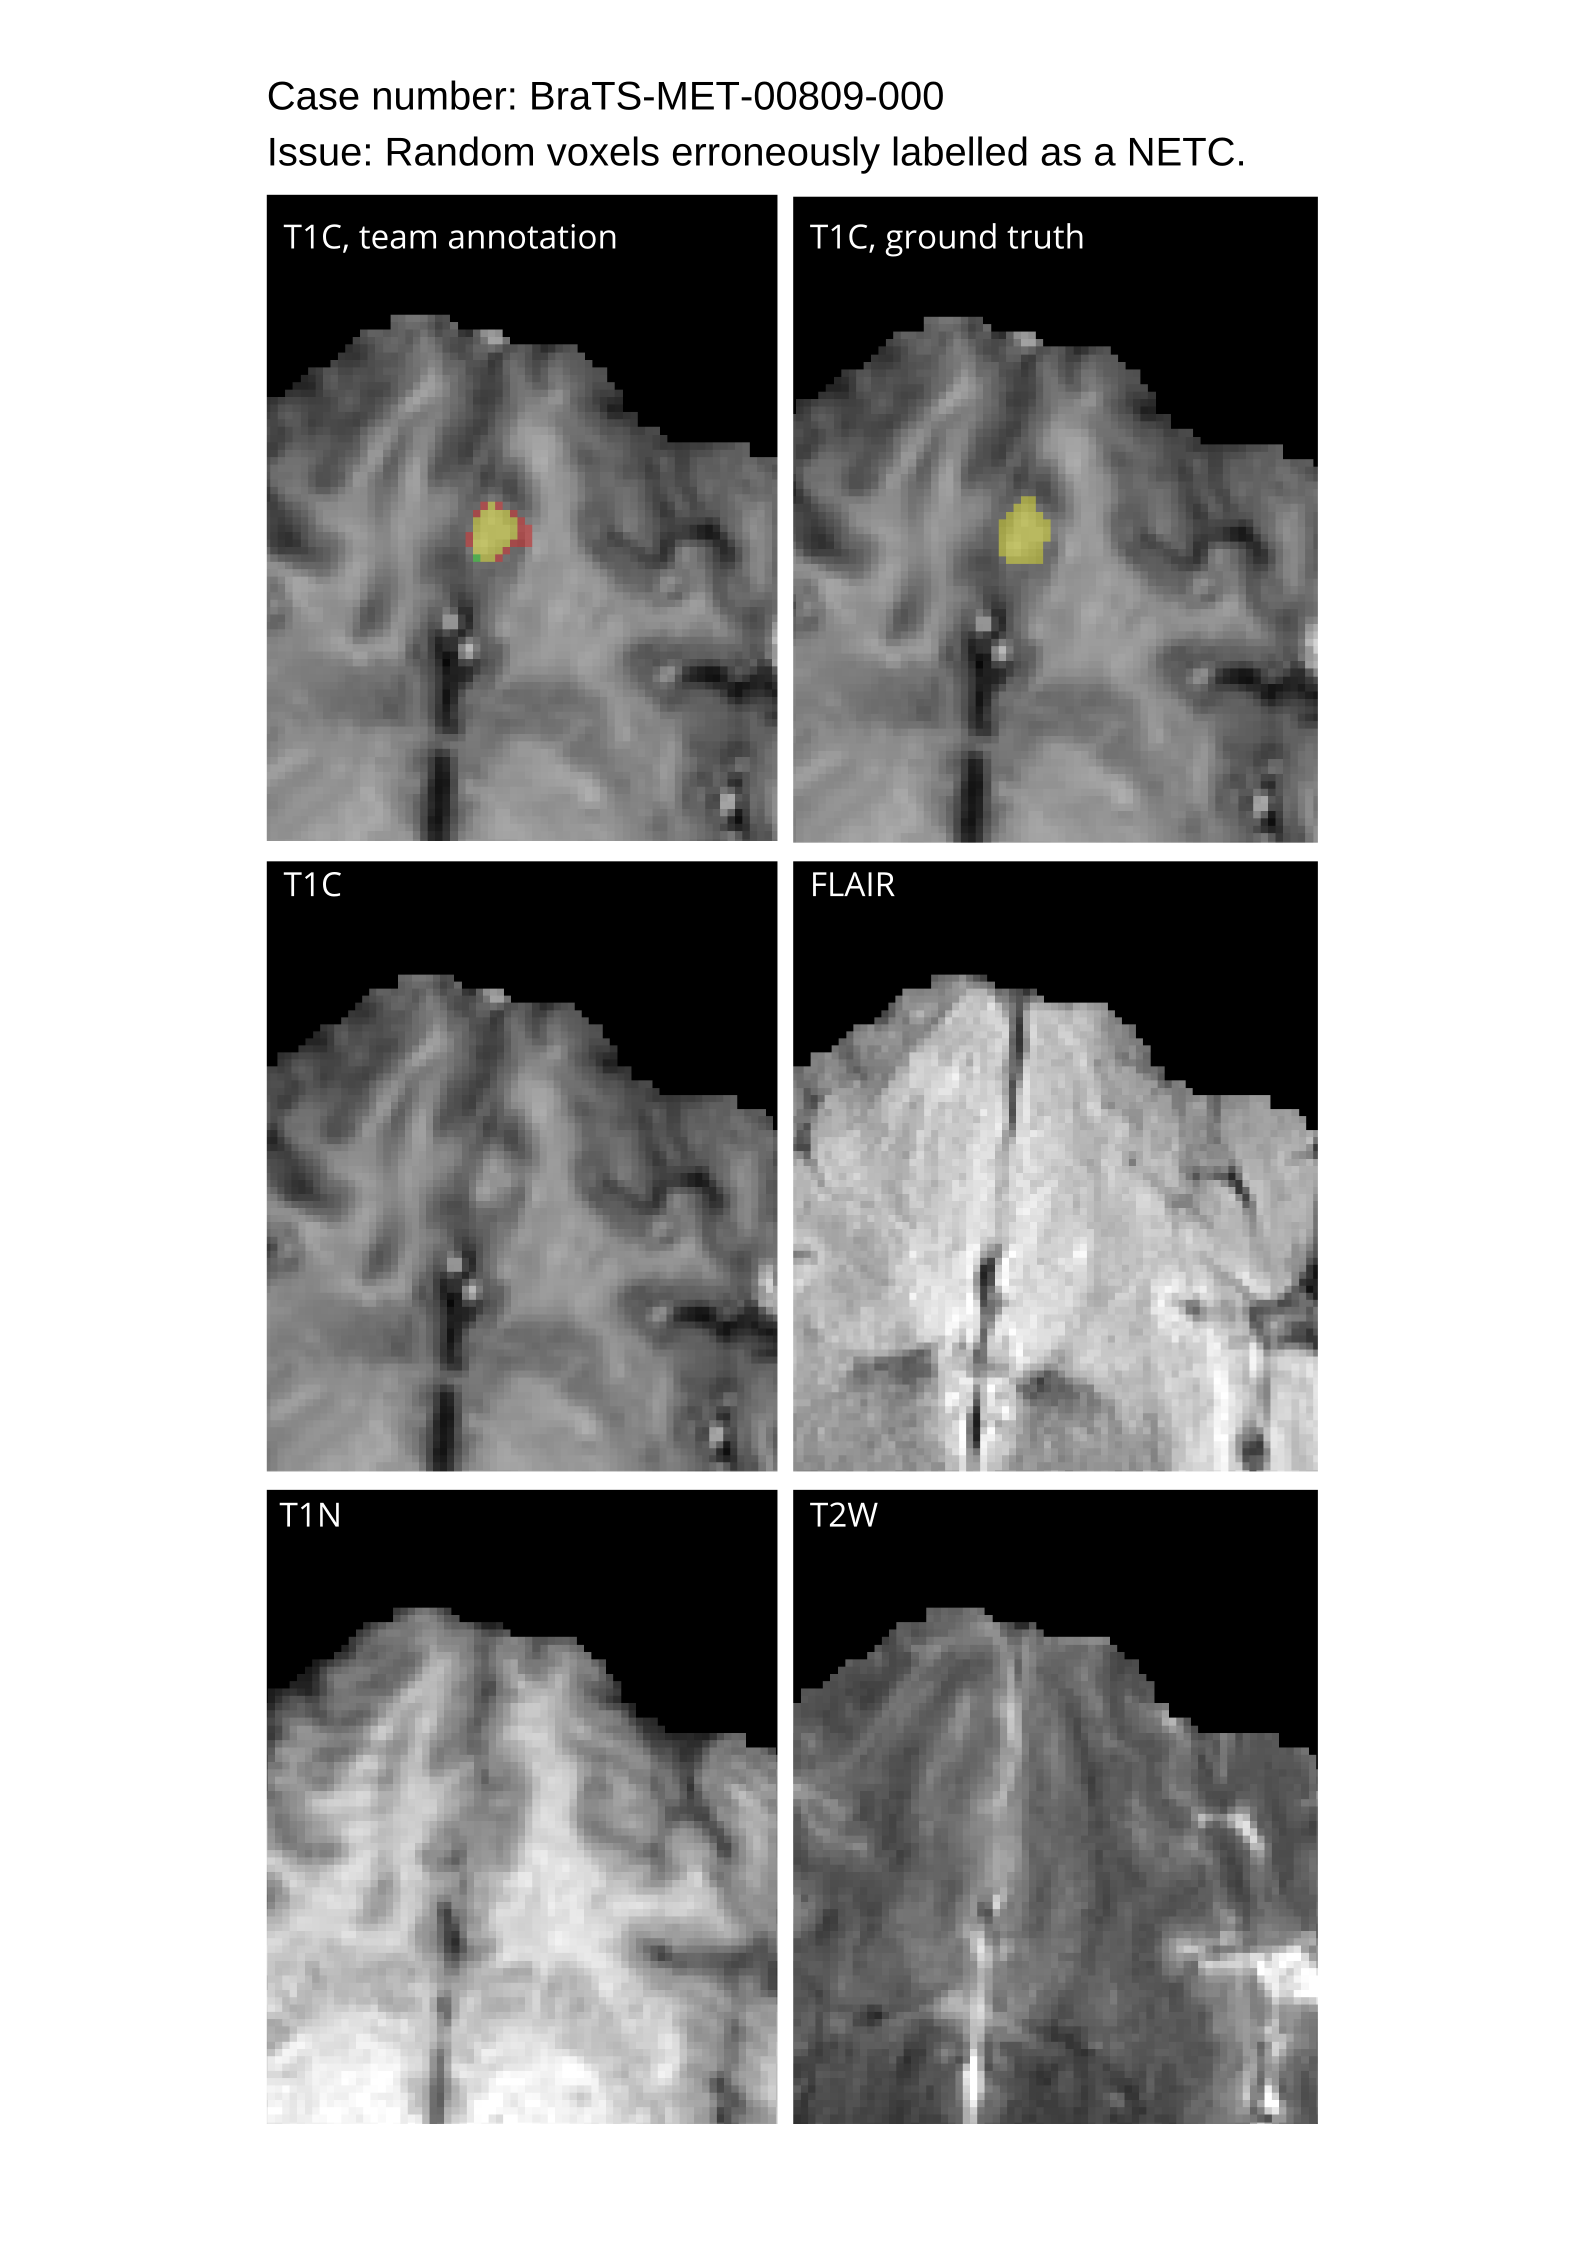

4.9 Common Errors of Automated Segmentations

Based on observations from previous BraTS challenges, common errors in automated segmentations were identified. The most typical errors in the current challenge included:

1. 1.

Automated algorithms missing small metastases. Enhancing metastasis was fused using the minority voting algorithm to aggregate all enhancing tumor voxels identified by the three algorithms. However, many small metastases were missed and were manually segmented by neuroradiology attendings.

2. 2.

Segmentation of white matter changes from microvascular disease. Peritumoral edema segmentations were checked by neuroradiology attendings and modified.

3. 3.

The segmentation of non-enhancing lesions that have intrinsic T1 hyperintensity. Voxels with intrinsic T1 hyperintensity were manually removed from ET segmentations.

These insights led to specific adjustments in the annotation process to enhance accuracy.